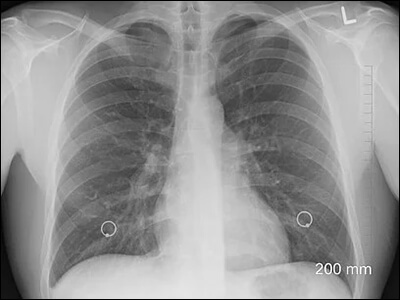

1) 폐색전증

호흡기계 중 가슴통증 원인이 되는 증상으로는 폐색전증을 이야기할 수 있습니다. 폐색전증은 폐에 혈액을 공급해주는 혈관이 막혀 혈액 공급이 줄어들거나 막히는 경우에 생길 수 있습니다. 이 경우 호흡곤란 및 가슴 통증을 유발합니다. 또한 숨을 들이마시거나 기침을 하게 되면 찌르는듯한 통증이 심해지며, 고열을 동반하는 경우도 있습니다.